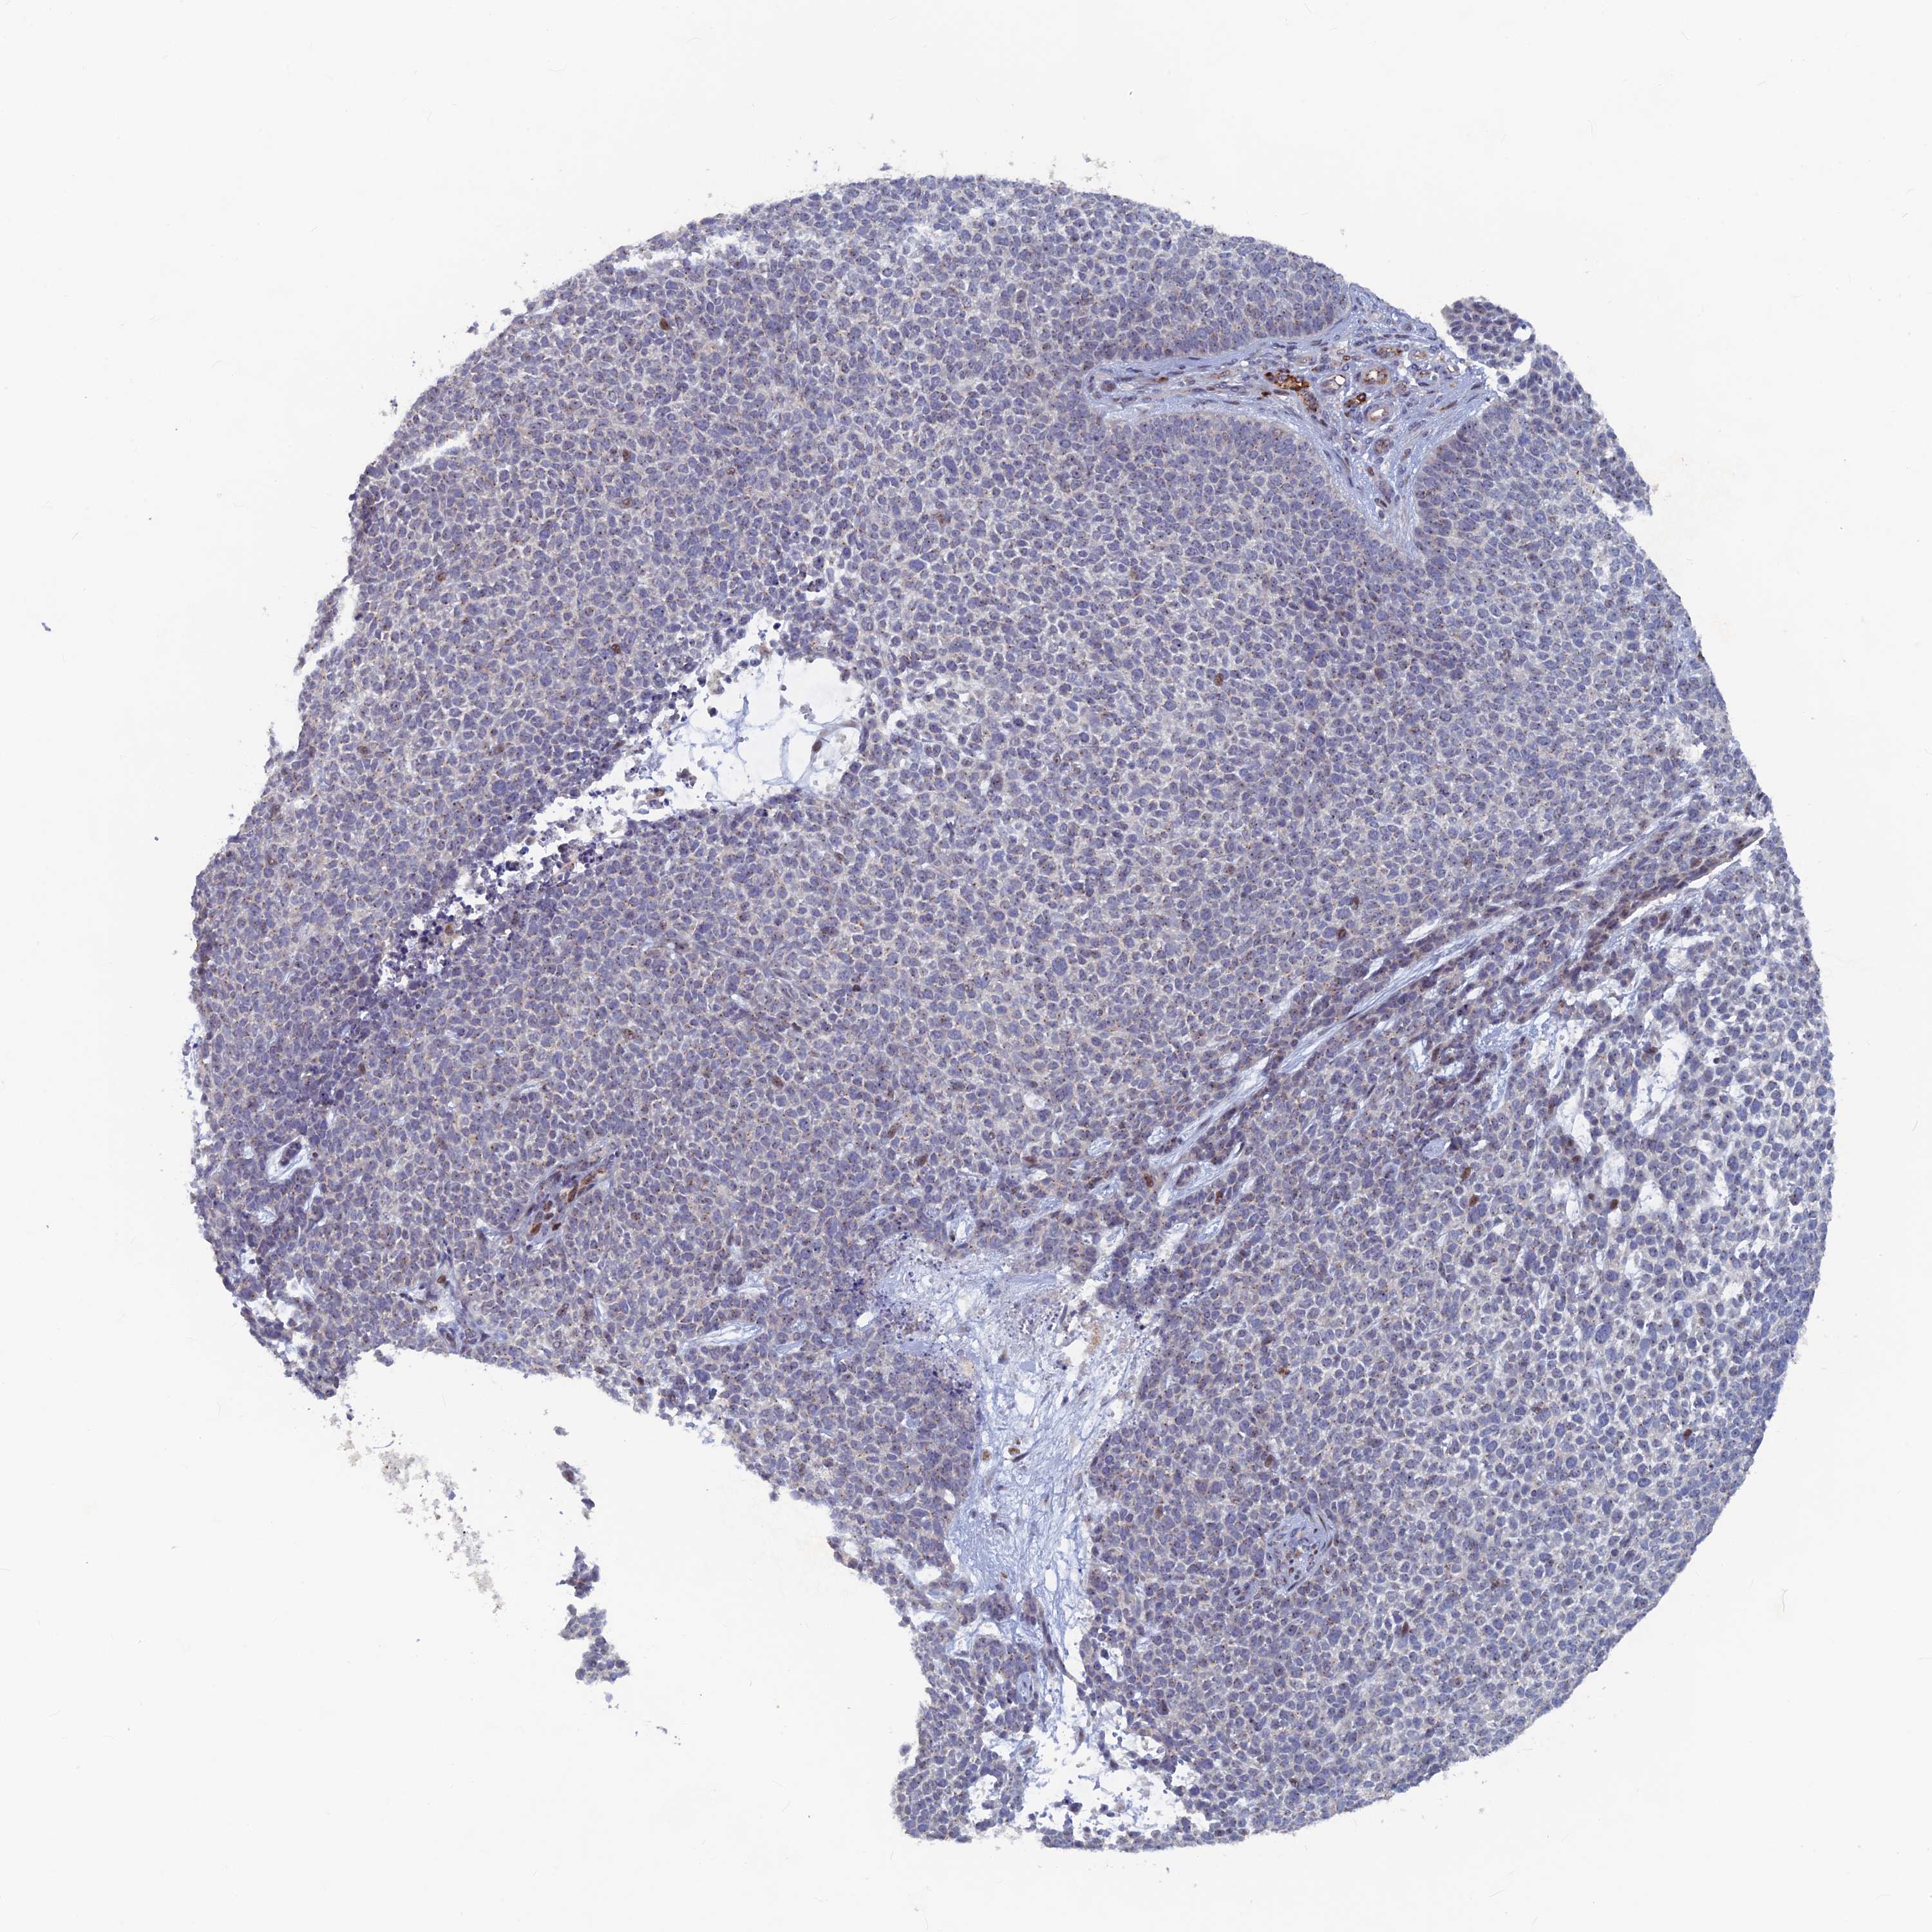

SKIN CANCER - Protein expressioni

A mouse-over function shows sample information and annotation data. Click on an image to view it in a full screen mode. Samples can be filtered based on level of antibody staining by selecting one or several of the following categories: high, medium, low and not detected. The assay and annotation is described here.

Antibody stainingi

Antibody staining in the annotated cell types in the current human tissue is reported as not detected, low, medium, or high, based on conventional immunohistochemistry profiling in selected tissues. This score is based on the combination of the staining intensity and fraction of stained cells.

Each image is clickable and will lead to virtual microscopy that enables deeper exploration of all samples and also displays staining intensity scores, fraction scores and subcellular localization as well as patient and tissue information for each sample.

Antibody HPA042456

Basal cell carcinoma

Squamous cell carcinoma, NOS

Squamous cell carcinoma, metastatic, NOS